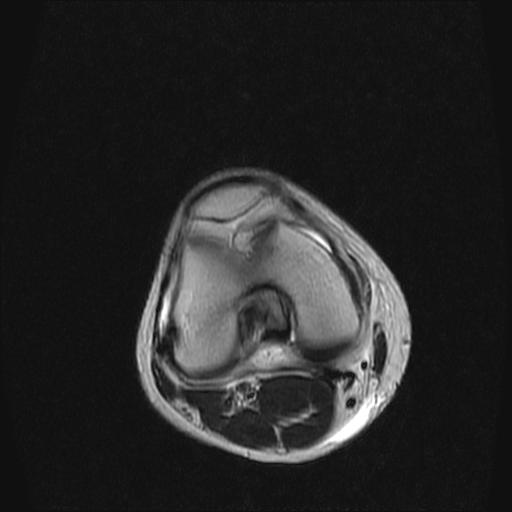

40岁男性,右膝关节外伤,x光平片示,髁间隆突撕脱骨折。

1、前交叉韧带撕裂;

2、外侧半月板后角撕裂;

3、关节腔积液。

半月板1-2级损伤   前交叉韧带撕裂伤   关节腔少量积液  诸骨未见新鲜外伤性改变

髁间隆突撕脱骨折;内侧副韧带损伤。

1、内侧副韧带撕裂;

2、前交叉韧带撕裂;

3、滑膜炎伴关节腔积液。

1、前交叉韧、内侧副韧带撕裂;

3、关节腔积液。4、髁间脊撕脱骨折。